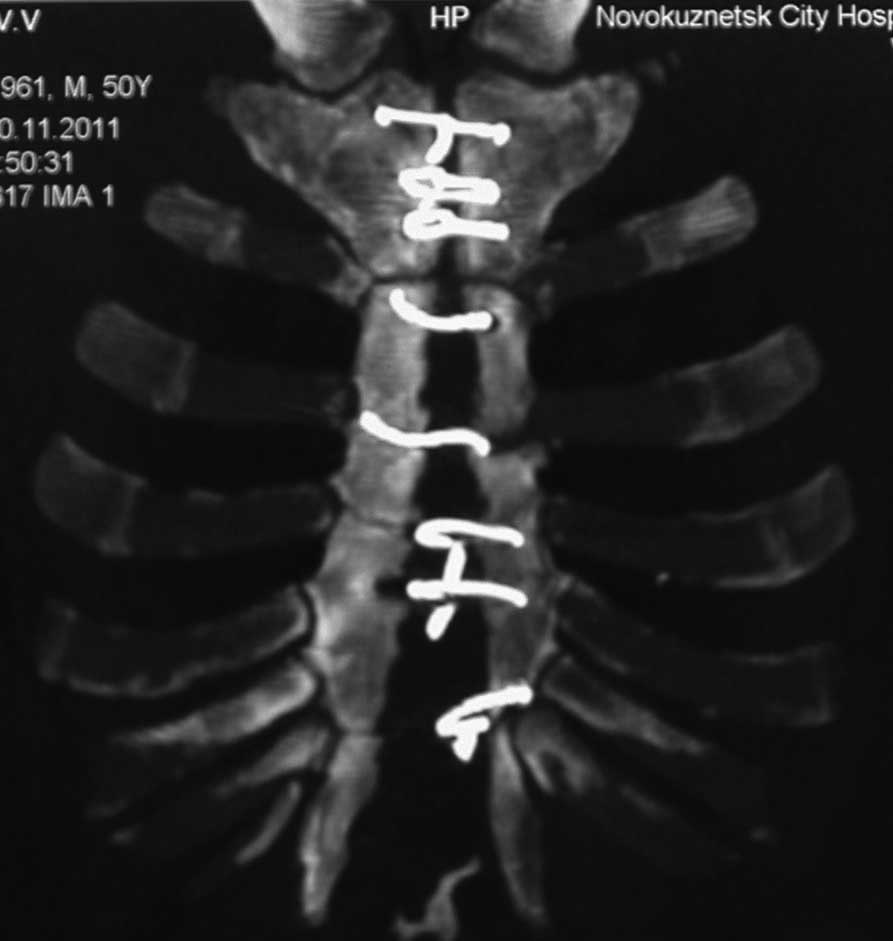

Sorry основной снимок

Добрый вечер, уважаемые Коллеги! Хочу поделиться опытом лечения ложных суставов грудины, осложнённых хроническим остеомиелитом. Все пациенты после аортокоронарного шунтирования. Фиксация грудины осуществлялась лавсановыми нитями. Основная проблема заключается во флотации грудины и необходимости применения аппаратов внеочаговой фиксации. Предложенный аппарат прост и состоит из комплектующих аппарата Илизарова и эндокорректора позвоночника Роднянского -Гупалова (именно крючки,которые фиксируются за дужки позвонков при сколиозе). Крючки вводятся в тело грудины посредством инструментов, которые предназначены для установки эндокорректора. Аппарат позволяет дать нужную компрессию, исключить флотацию и добиться сращения грудины. Предварительно делается полноценная санация очага остеомиелита. В одном случае производилась костная аутопластика из гребня подвздошной кости - был большой диастаз.